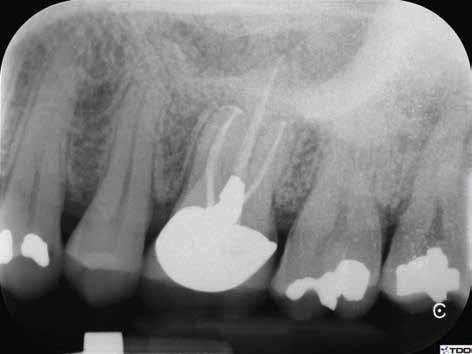

6. a–d. ábrák: A bal alsó második nagyőrlőfogon (3.7) kialakított konzervatív hozzáférési nyíláson keresztül végzett endodonciai kezelés lépései. A mezialis gyökér jelentős mértékben görbült. A gyökértömés hidraulikus kondenzációs technikával készült.

b. ábrák: A jobb alsó első nagyőrlőfogon (4.6) lévő cirkóniumkoronán keresztül elvégzett endodonciai kezelés. A hozzáférési nyílás kialakítása a lehető legkonzervatívabb módon történt. A gyökértömés hidraulikus kondenzációs technikával készült.

egyszerű obturációs technika, az anyag viszkozitási tulajdonságai és a pulpakamra viszonylag egyszerű tisztíthatósága a kezelésünk prognózisának veszélyeztetése nélkül teszi lehetővé az endodonciai beavatkozások lehető legkonzervatívabb módon történő kivitelezését. A bemutatott esetek ellátása során az Aurum Blue rendszert (Meta Biomed) használtuk a gyökércsatornák megmunkálására, míg a gyökértömés elkészítése során hideg hidraulikus kondenzációs technikát alkalmaztunk a kalcium-szilikát alapú CeraSeal (Meta Biomed) sealer felhasználásával (8. ábra).

Esetbemutatás (2., 3.)

Mindkét esetben irreverzibilis pulpitis miatt vált szükségessé a fogak endodonciai kezelése (6. a-d. és 7. a-b. ábrák). Az esetek ellátása során mindvégig minimálinvazív megközelítést alkalmaztunk. A hozzáférési nyílás kialakításától kezdve az endodonciai kezelés befejezését követő csonkfelépítésig, minden beavatkozás ennek megfelelően történt.